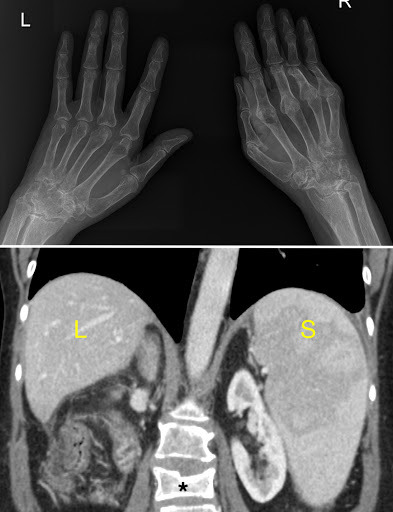

dens involvement in RA

Bad RA in the hands

RA